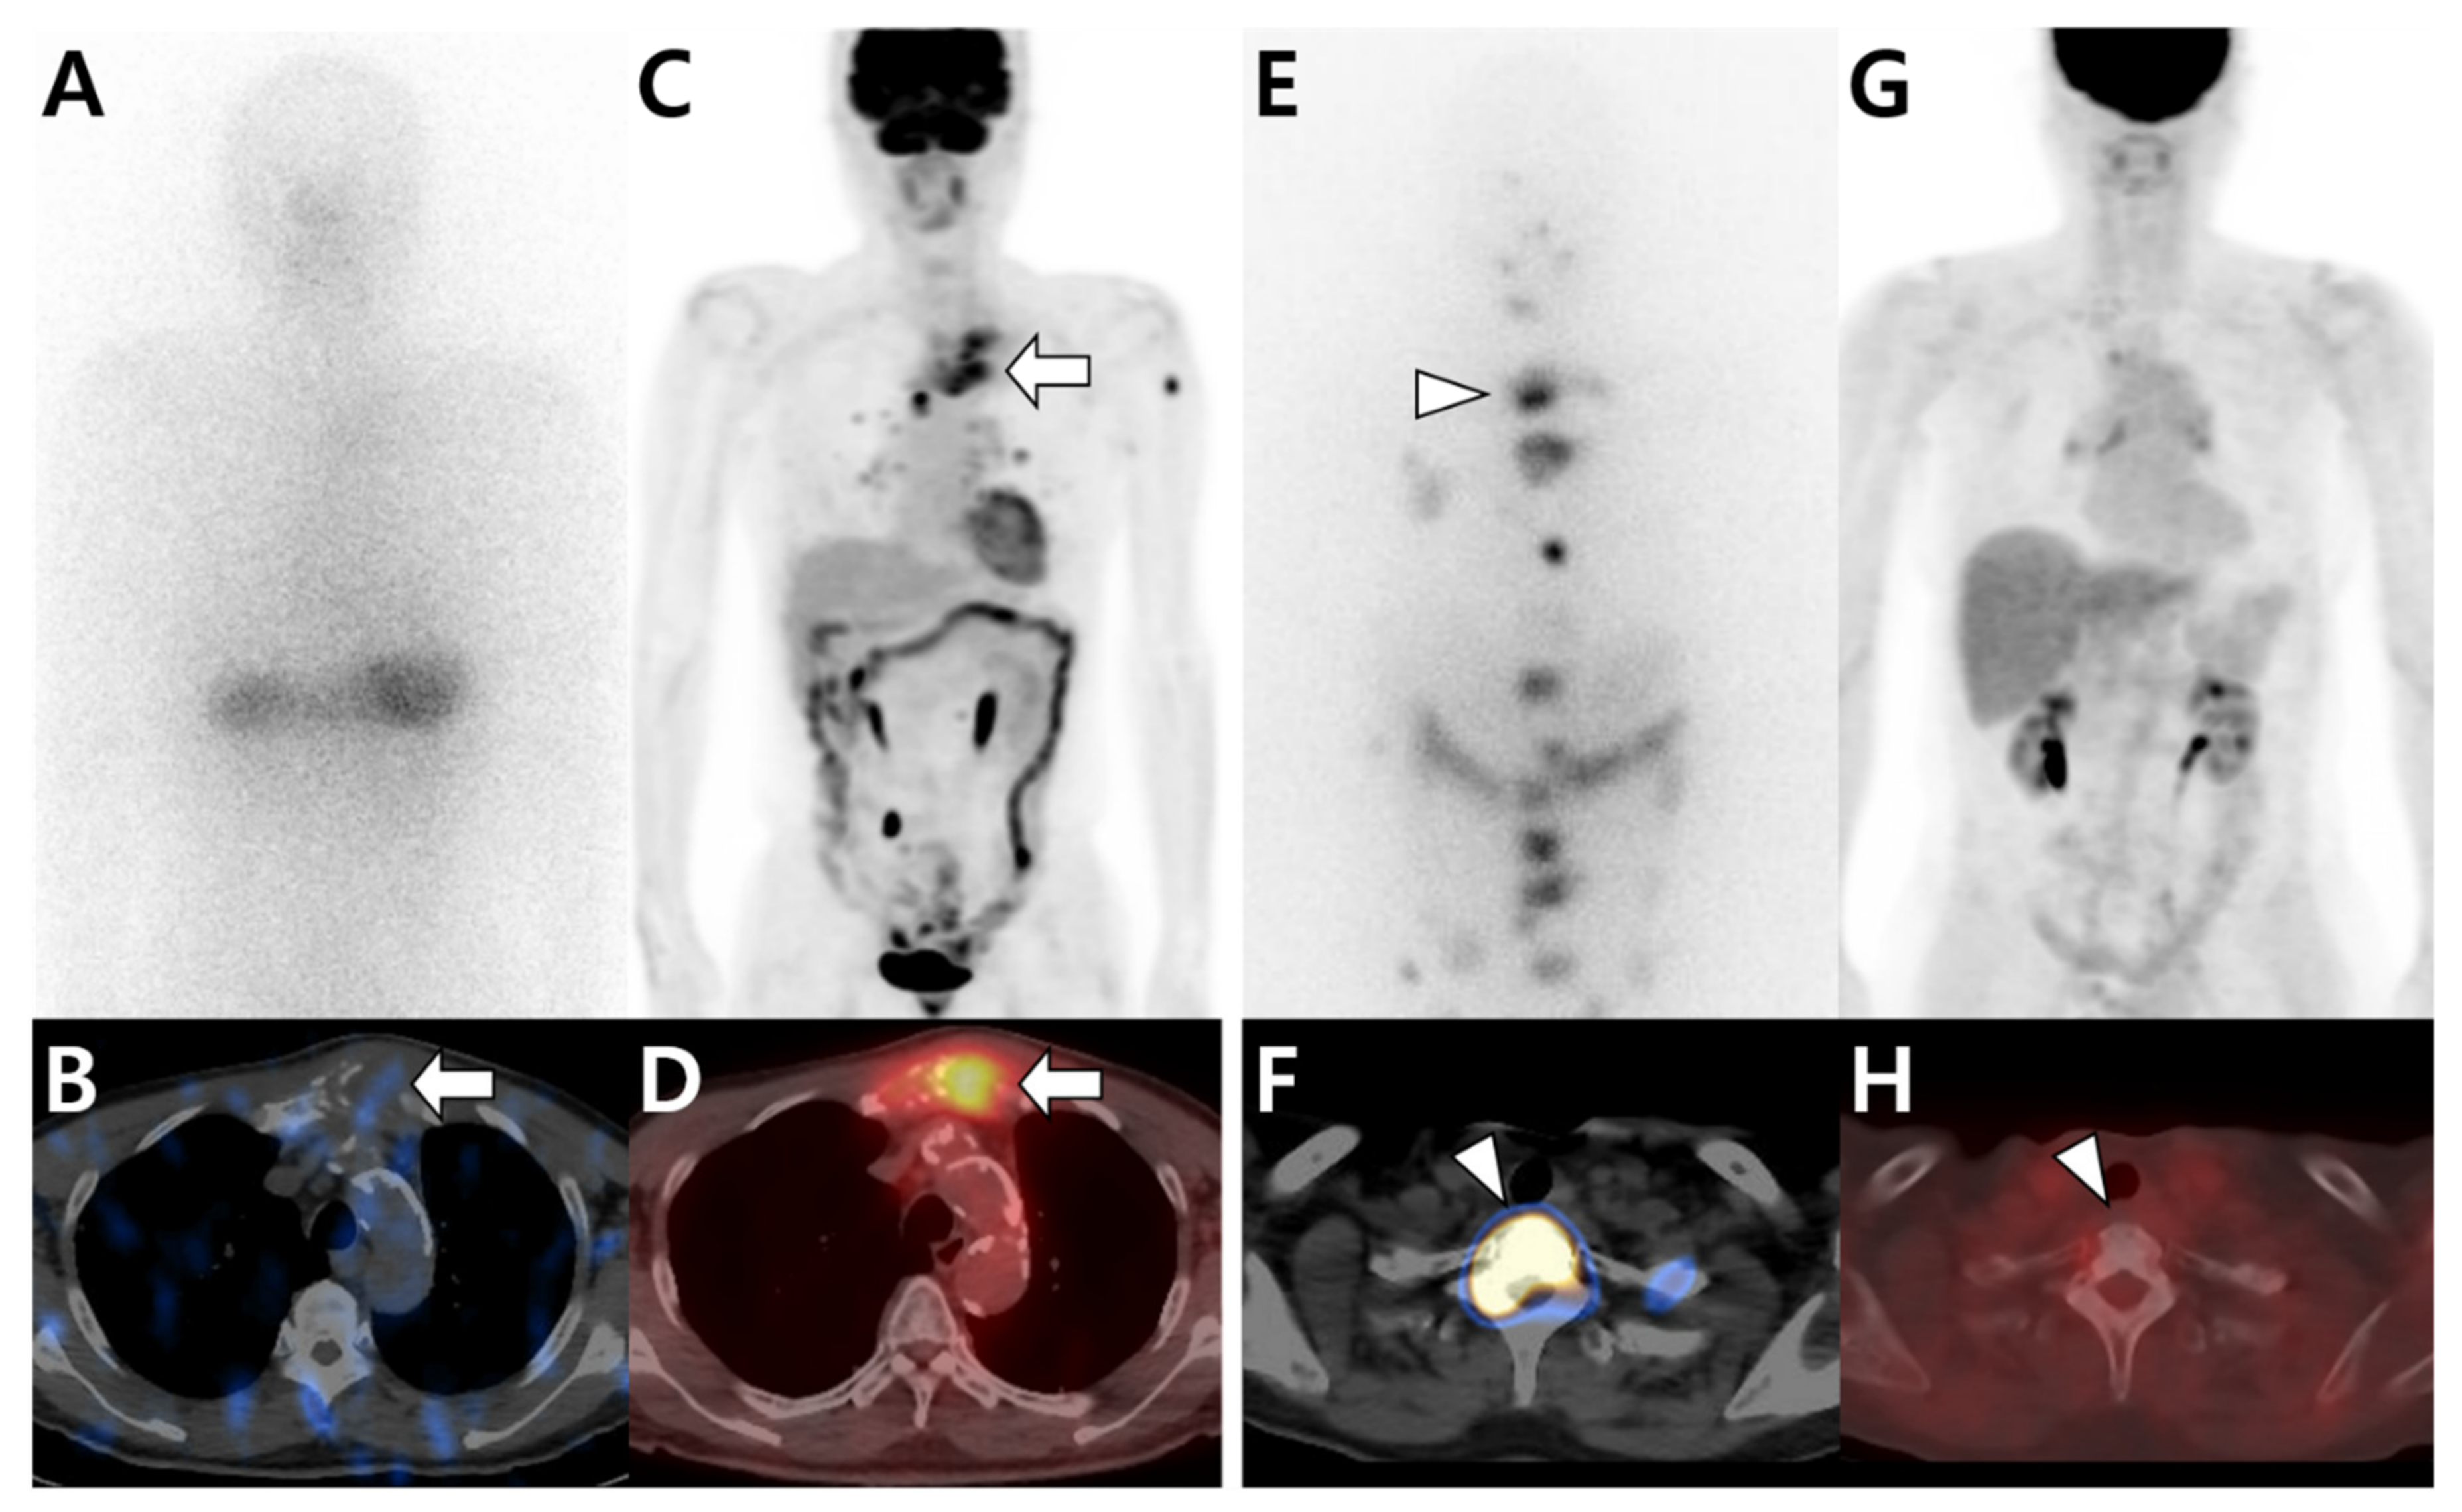

3.1. Multimodal Imaging According to the Primary Tumor Site and Histologic Type

3.2. Multimodal Imaging According to the Differentiation Status of the Primary Tumor